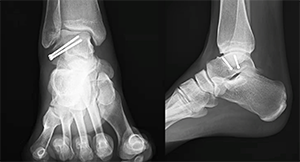

Front and side views of the same lateral process fracture treated with 2 screws for fixation